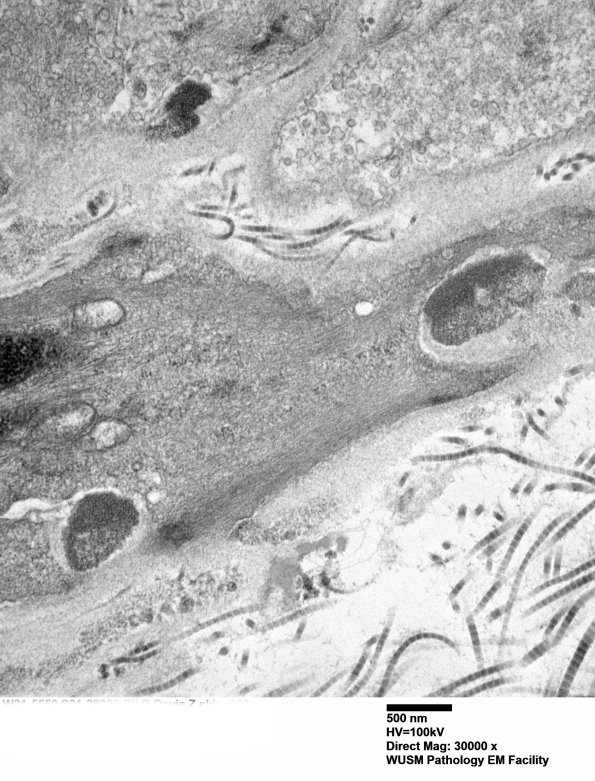

Washington University Experience | MYELIN (NON-IMMUNE MEDIATED) | CADASIL | 11C3C (Case 11) BlkD skin EM 022 - Copy

11C3C (Case 11) BlkD skin EM 022 - Copy

11C3C Several GOMs. (electron micrographs)